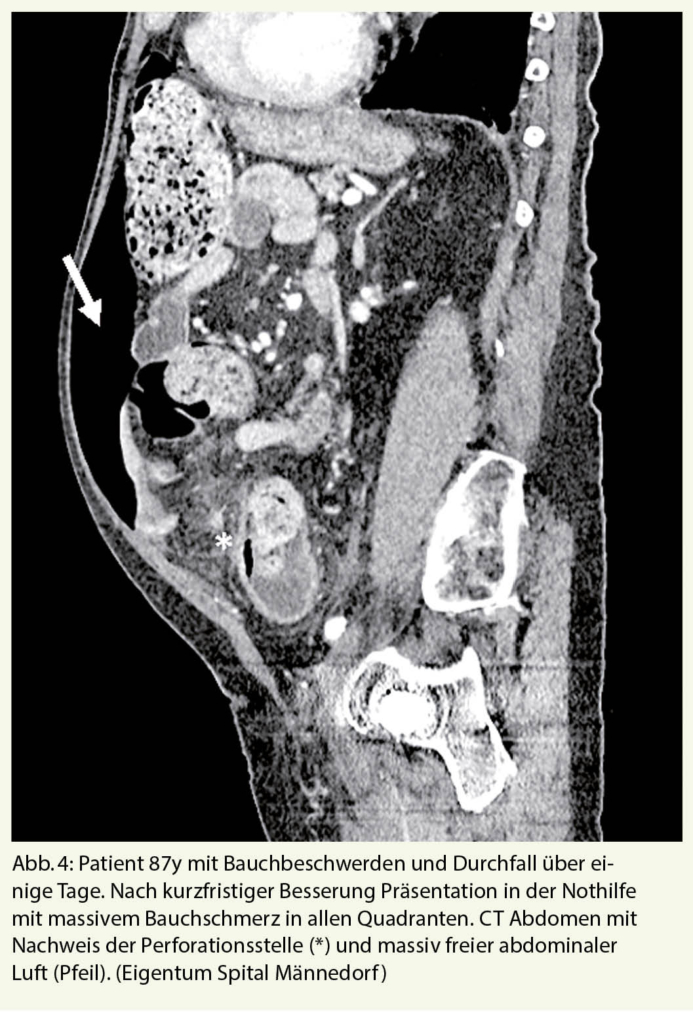

Die akute Appendizitis ist bei älteren Patienten mit akuten Bauchschmerzen seltener als bei jüngeren Patienten, wobei allerdings Morbiditäts- und Mortalitätsraten höher sind (Abb.3). Zwischen 5 und 10 % der Fälle von Appendizitiden treten bei Menschen über 65 Jahren mit einer Mortalität von 10-20 % und einer Morbidität von 30-60 % auf. Dafür ursächlich sind alterstypische Komorbiditäten sowie häufig eine Therapieverzögerung durch atypische Symptome mit dadurch bedingt höherer Perforationsrate (9, 10).

Die akute Divertikulitis des Dickdarms ist eine der häufigsten Erkrankungen, die zu einer Einweisung in den Notfall führen. Bei mehr als 50 % der über 65-Jährigen liegt eine Divertikulose vor, aus der in 10-25% eine akute Divertikulitis entstehen kann (13, 14). Auch bei einer perforierten Divertikulitis können typische Schmerzen im linken Unterbauch mit Abwehrspannung fehlen, so dass auch hier nur eine Computertomographie des Abdomens zur Klärung der Situation beiträgt. Nicht selten präsentieren sich ältere, immungeschwächte Patienten primär mit einer frei perforierten Sigmadivertikulitis, die mit einer massiven eitrigen Peritonitis und entsprechend hoher perioperativer Letalität einhergehen kann (Abb. 4)